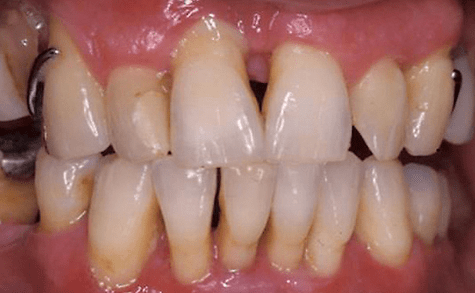

Parodontalpathogene Bakterien sind in der Lage, ausgehend vom Zahnfleischsulkus in die parodontalen Gewebe einzudringen.1 Durch den damit verbundenen Verlust der epithelialen Integrität kann in der Folge die Zahnfleischtasche entstehen und die Gefahr einer Bakteriämie erhöht sich. In­zwischen ist bekannt, dass vorübergehende Bakteriämien beim Menschen nach dem Zähneputzen und nach Anwendung von Zahnseide entstehen können.3,5,19 Zunehmend wird in der Literatur auch über einen möglichen pathogenetischen Zusammenhang zwischen latenten chronischen Entzündungen und Störungen des Fettstoffwechsels bzw. Herz-Kreislauf- Erkrankungen berichtet.2,10,11,21 So gilt inzwischen die Zahnfleischtasche als eine wichtige bakterielle Eintrittspforte anaerober Bakterien bzw. verschiedener lokaler Zytokine in das Herz-Kreislauf-System. Für die destruktiven Prozesse an den parodontalen Geweben und am alveolären Knochen sind u. a. Agregatibacter actinomycetemcomitans und Porphyromonas gingivalis verantwortlich (Abb. 1a–b). Es gibt aber zunehmend auch Hinweise, dass gramnegative orale Bakterien in der Ätiologie der Arteriosklerose eine Rolle spielen.6 Zambon et al. wiesen Porphyromonas gingivalis in arteriosklerotischen Plaques bei Patienten mit koronarer Herzkrankheit nach.21 Genco et al. sprechen von einem erhöhten Risiko für Myokard infarkte beim Nachweis von Porphy romonas gingivalis und Tannerella forsythia in der Zahnfleischtasche.2

Die parodontalen Gewebe sind durch die parodontalpathogenen gramnegativen Anaerobier infiziert8,13,20 und es resultieren zum Teil erhebliche Gewebs- und Knochendestruktionen, nicht selten auch schon bei jungen Erwachsenen. Bei der schweren aggressiven und chronischen Parodontitisform ist es häufig, dass die Bakterien noch nach alleiniger mechanischer Therapie persistieren.12 Deshalb werden Therapiekonzepte benötigt, die die mechanische und antibiotische Therapie sinnvoll miteinander verknüpfen,4 um die pathogenen Bakterien möglichst an allen betroffenen Stellen zu eradizieren und so die „Eintrittspforte“ Parodont umfassend zu sanieren. Bisher gibt es unterschiedliche Auffassungen, wann mit der Antibiotikatherapie begonnen werden sollte.